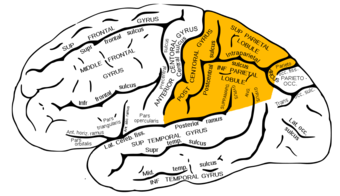

الفص الجداري parietal lobe، هو أحد الفصوص الرئيسية الرابعة في قشرة المخ لدى الثدييات. يقع الفص الجداري فوق الفص القذالي وخلف الفص الجبهي والتلم المركزي.

يدمج الفص الجداري المعلومات الحسية بين الحواس المختلفة، ومنها الحاسة المكانية والملاحة (استقبال الحس العميق)، منطقة الاستقبال الحسية الرئيسية للملس (الاستقبال الميكانيكي) في التلم الأوسط داخل التلفيف خلف المركزي،[1] والمجرى الظهري للجهاز البصري. المدخلات الحسية الرئيسية الواردة من [[جلد|اللجلد (مستقبلات اللمس، درجة الحرارة، والألم)، ناقلة إياها عبر المهاد إلى الفص الجداري.